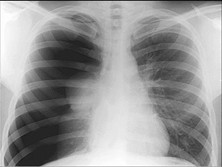

开放性气胸

开放式气胸是指导气胸漏气通道持续开放,气体随呼吸进出胸膜腔的气胸。大多数情况下,...

胸部B超、胸部CT、X线平片